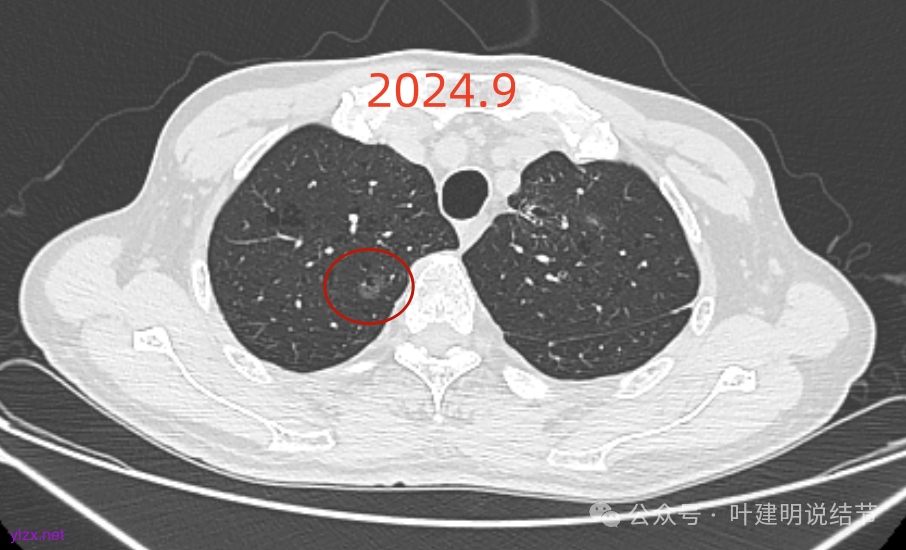

再看2024年9月复查的:

右上的仍小而淡,轮廓仍是清楚的。

左上的病灶略显模糊,密度不太纯,较前相仿。

再看2024年9月的:

右上的较前略增大,且有空泡征较豙明显些,肿瘤的成分仍是纯磨密度。

左上病灶也是较为纯的,边缘不光滑,大小似乎略大一点点,不太显著。